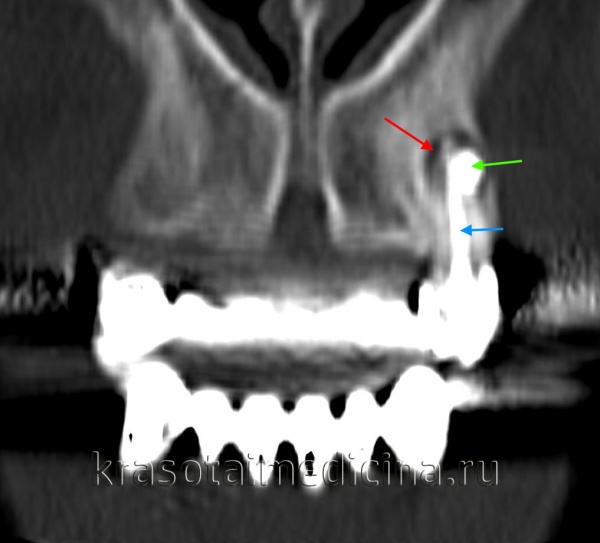

(Слева) На периапикальной рентгенограмме нижней челюсти справа между первым и вторым премоляром (наиболее типичная локализация) определяется боковая периодонтальная киста. Обратите внимание, что киста имеет классический вид слезы.

(Справа) На сагиттальной трехмерной реконструкции (КЛКТ) между первым премоляром и клыком нижней челюсти определяется многокамерное объемное образование. Была выполнена биопсия, подтвердилась гроздевидная одонтогенная киста (ГОК).

КТ челюстно-лицевой области. Радикулярная киста (красная стрелка) вблизи корня левого клыка верхней челюсти, состояние после эндодонтического лечения (синяя стрелка – филлер в корневом канале), избыток филлера за пределами верхушки зуба (зеленая стрелка).